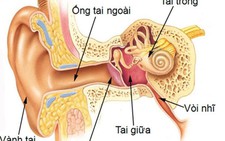

Bất cứ ai cũng có thể bị bệnh lý viêm tai ngoài, tuy nhiên tần suất mắc bệnh cao nhất gặp ở trẻ em. Do đó chúng ta cần phân biệt bệnh lý viêm tai ngoài với bệnh lý viêm tai giữa cũng là một bệnh khá thường gặp, xảy ra sau khi trẻ bị những đợt nhiễm trùng hô hấp trên như cảm thường, viêm mũi, viêm xoang…

Bình thường ống tai ngoài của chúng ta có một hàng rào bảo vệ đó là ráy tai. Ráy tai được hình thành do sự bài tiết của các tuyến ở da ống tai. Chúng tạo nên một lớp màng mỏng, không thấm nước, lót mặt trong ống tai.

Môi trường acid của ráy tai cũng giúp ngăn chặn sự phát triển của các vi khuẩn. Ráy tai cũng giúp giữ lại bụi bẩn, các tế bào da chết và đẩy dần những thành phần này ra bên ngoài.

Ngoài ra, các sụn vành tai cũng góp phần ngăn chặn sự xâm nhập của các vật thể lạ vào bên tỏng ống tai. Một khi hàng rào bảo vệ này bị phá vỡ sẽ tạo điều kiện thuận lợi cho các tác nhân gây bệnh như vi khuẩn, virus hoặc nấm xâm nhập, phát triển và gây bệnh.